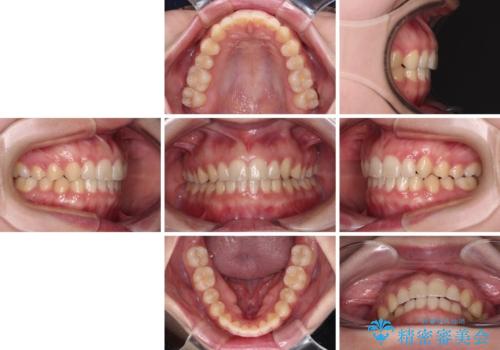

- 八重歯を気にして来院された患者様です。

八重歯のために乳歯が残存していたため、乳歯を抜去して八重歯となっている犬歯を歯列に収めることとしました。

八重歯の移動量が多くなるため、インビザラインと併用してワイヤー矯正を行い、八重歯を改善した後に、上下歯列をインビザラインで整えることとしました。

犬歯は歯根が長くて太いため移動に時間がかかる上に、周囲の歯が八重歯に寄ってきてしまうため、仕上がるまでに期間がかかりました。